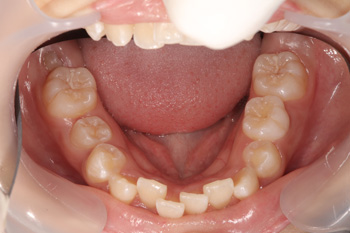

歯列育形成によるお子様の叢生の歯並び治療の症例

Before

装置は取り外しが可能な拡大装置という顎を広げる装置を使います。顎が広がった時点で、ブラケットにより歯並びの調節を行います。

小児矯正と成人矯正の違いは、歯を並べるスペースを拡げて作るか抜いて作るかというところがあります(※成人後も抜歯無しで並べれる場合もあります)。大人になってからの矯正では外科手術以外顎の骨格を変えることはできませんのが、Ⅰ期矯正を行うことで歯を並べるスペースを確保し、抜歯せずに歯を並べることが可能となります。約2年で、歯を並べるスペースを確保し、きっちり歯も並びました。

治療の内容 歯列育形成によるお子様の叢生の歯並び治療。

期間・回数 2年・23回(カウンセリング・検査含む)

費用 自由診療:歯列育形成 総額 580,000円(調整料36回分含む)税込701,800円